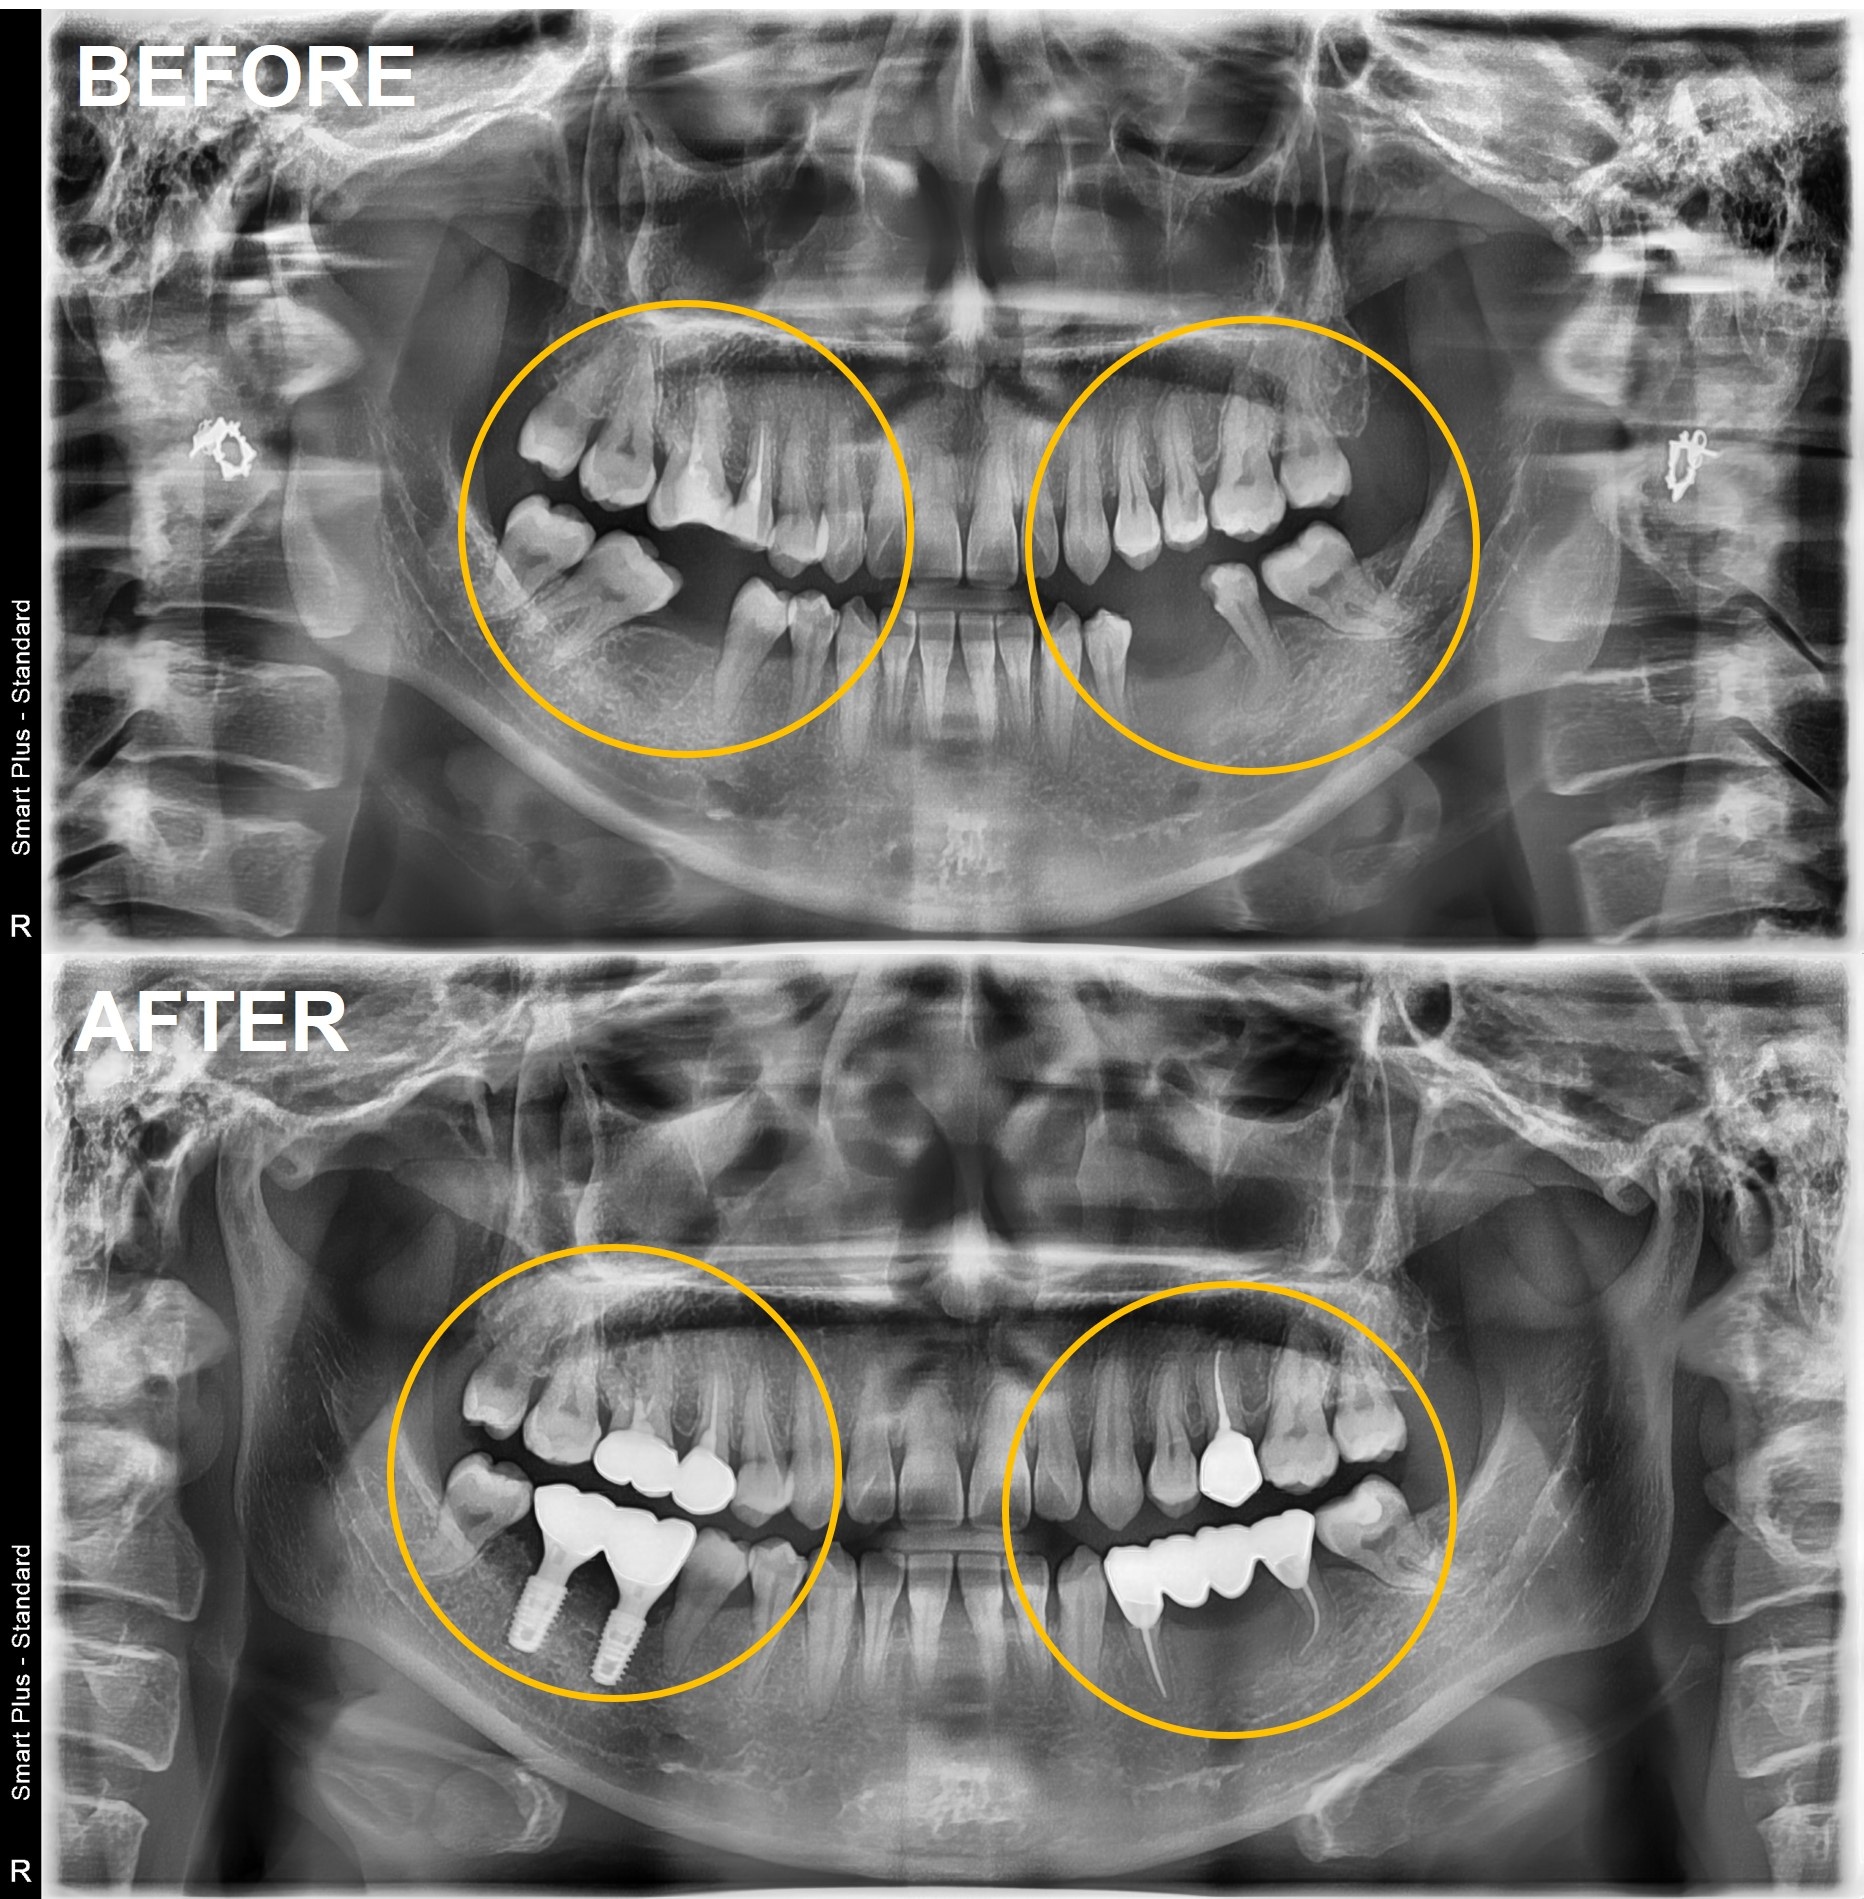

2023년 1월부터 시작된 치료는 총 4개의 임플란트 식립과 브릿지 제작, 그리고 교합 조정 과정을 거쳐 7월까지 약 6개월간 진행되었습니다.

쏠렸던 치아들은 제자리로 돌아갔고, 교합 평면은 균형을 이루었으며, 양쪽 어금니가 동시에 닿으면서 턱관절의 부담도 줄어들었습니다.

단순히 임플란트 4개를 심는 것으로 해결될 문제가 아니었습니다.

이 모든 것을 고려하지 않고 임플란트만 심는다면 결국 또다시 문제가 생길 것이 분명했습니다.